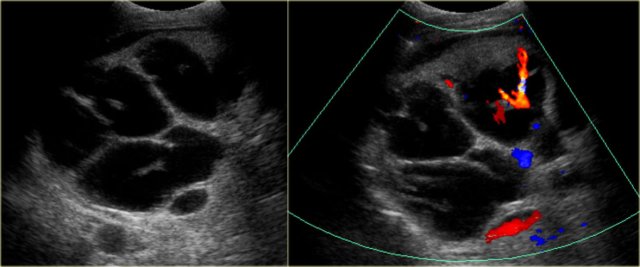

A very important sign is the central dot sign.

The central dot corresponds to the portal vein that is surrounded by dilated bile ducts.

On the left we see a dot within the dilated ducts.

When we put on the color doppler, we will notice that these structures contain blood flow and represent portal veins.

On the left CT-images of the same patient.

Notice the central dot sign and the segmental involvement.

This patient has cirrhosis with splenomegaly due to portal hypertension.